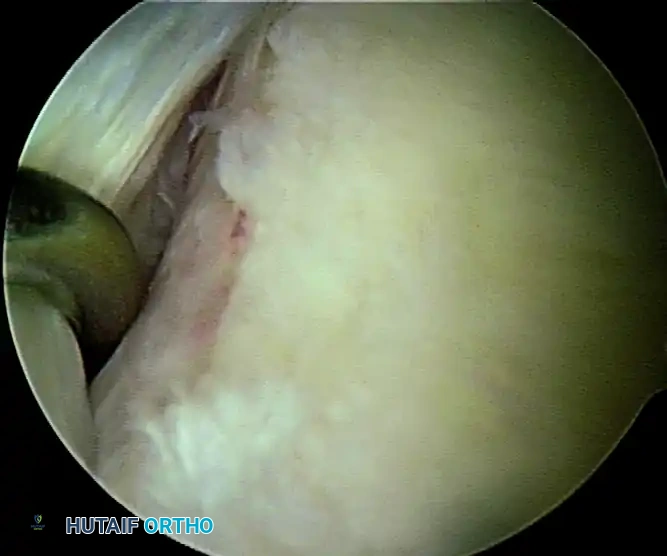

5. Recreating the Anterior Bumper

Proceed superiorly, placing the second and third double-loaded anchors. Firmly secure the sutures, compressing the capsuloligamentous complex to the abraded bone surface. This "loop and knot fixation" rolls the tissue up onto the glenoid face, recreating a robust anterior soft-tissue bumper.

D, Knots tied re-creating soft tissue bumper.

B, Restored anterior labral bumper (arthroscopic view).

C, Restored anterior labral bumper (alternate angle).

Final Construct Verification

Evaluate the final repair. The drive-through sign should be eliminated, the humeral head should be centered on the glenoid, and a prominent anterior bumper should be visible.